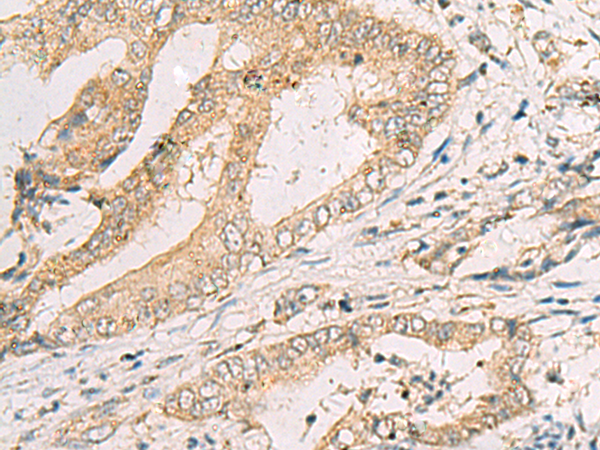

分类: 科研抗体货号: P10357别名: GNT-IV; GNT-IVB应用: IHC反应种属: Human, Mouse